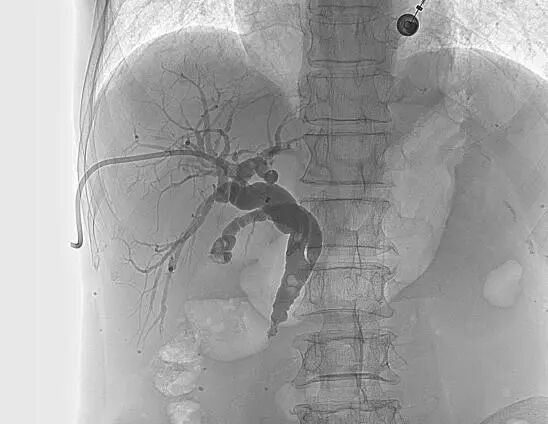

【经皮肝穿刺胆道引流术】

在X线透视引导下穿刺扩张的肝内胆管并置入引流管,可以快速引流淤积的胆汁,减轻黄疸、保护肝功能,为后续治疗创造条件。优点在于见效快,能快速退黄和控制胆道感染。缺点在于需长期携带引流管并定期更换,生活质量降低,且胆汁无法进入肠道,影响消化功能。